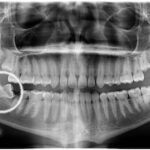

Caso de bruxismo severo, que ha producido un grave desgaste dental

El bruxismo es el hábito oral que consiste en el apretamiento, rechinamiento o frotamiento de los dientes de manera anormal e involuntaria. Puede ocurrir tanto por el día como por la noche, siendo durante el sueño lo más común.

Los pacientes son raramente conscientes de su propio hábito de apretamiento, pero es una causa común del desgaste dental, la movilidad dental por sobrecarga, dientes fracturados y el dolor muscular.

El bruxismo es una actividad parafuncional, no necesariamente patológica, pero en pacientes con un bruxismo severo es necesario su diagnóstico y tratamiento.